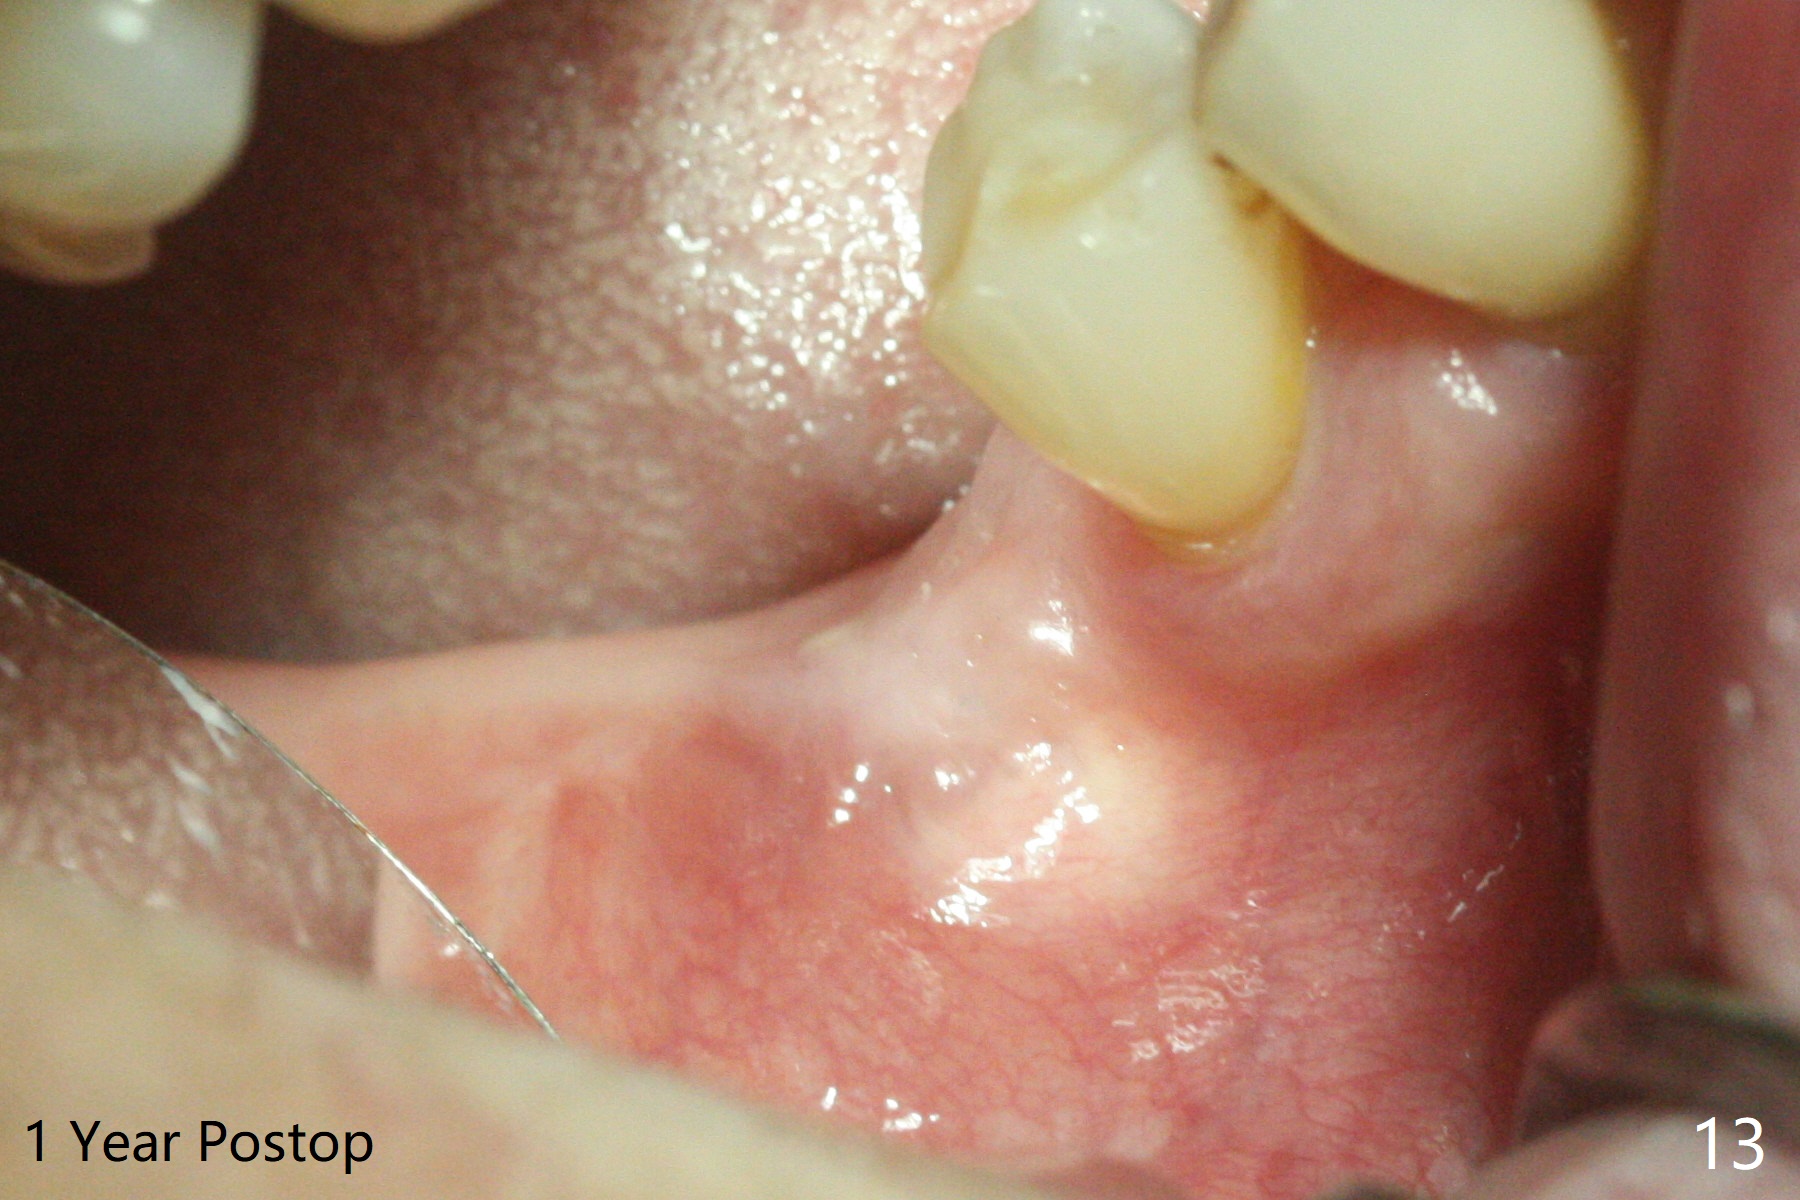

There are signs of periimplantitis at #30 eleven months postop (Fig.1 (* bone loss)). The bony defect (Fig.2) will be filled with allograft mixed PRF liquid to form sticky bone (Fig.3,4), followed by PRF membrane (not shown) and a piece of 6-month membrane (Fig.5). A hole is cut so that the 6-month membrane can slide down the abutment (Fig.2,5 A) to cover the bone graft around the implant (Fig.2,7 I). Setting acrylic is applied around the abutment and neighboring teeth for further protection and holding (Fig.8). The periimplantitis does not resolve nearly 7 months post graft. The implant will be removed. Prepare UF extra wide kit and try to insert 6.5 or 7.0 mm tap. Also prepare sticky bone and Cytoplast for wound closure. Implant removal involves surgical handpiece, 6.2/7 mm trephine bur, elevators, and implant driver. The defect is large (Fig.9) with the low buccal crest (Fig.10) and bone graft with PRF ("sticky bone") is placed, covered by PRF and 6-months membrane (Fig.11). The next implant will be placed with guide. If oral hygiene is not ideal, choose a bone level implant. The middle of the wound dehiscences slightly 8 days postop (Fig.12), accounting for mild loss of bone graft 1 year postop (Fig.14). The keratinized gingiva is apparently wide 1 year postop (Fig.13). There is mild loss of bone graft in the middle of the superficial area (Fig.14). The buccal plate seems to regenerate 1 year postop (pandemic delay, Fig.15).